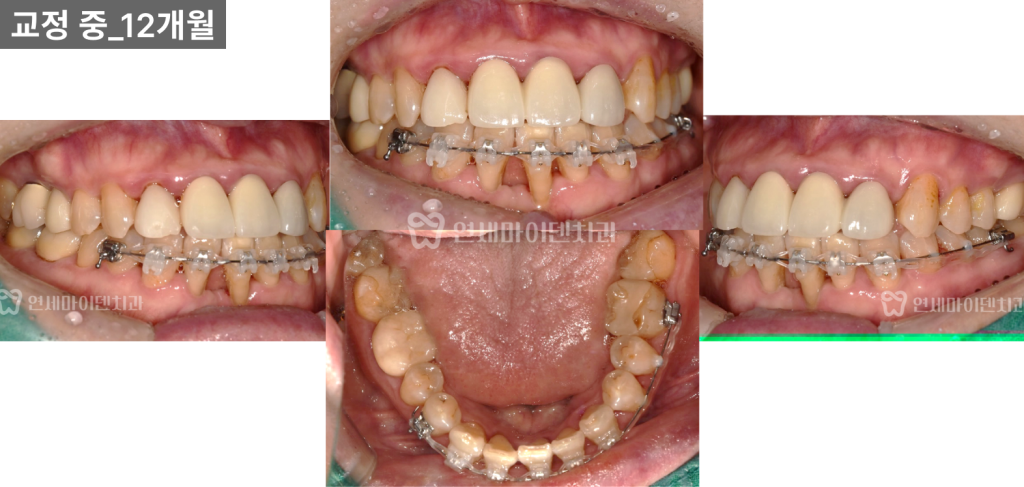

치료 과정의 단계별 변화

발치 후 치아 교정 장치를 부착하고

배열을 시작했습니다.

치료 중 심미적인 불편함을 최소화하기 위해

임시 레진을 보충하며 진행했습니다.

12개월 차

공간이 상당 부분 닫히면서

송곳니 위치도 정상적인 배열에 가까워졌습니다.